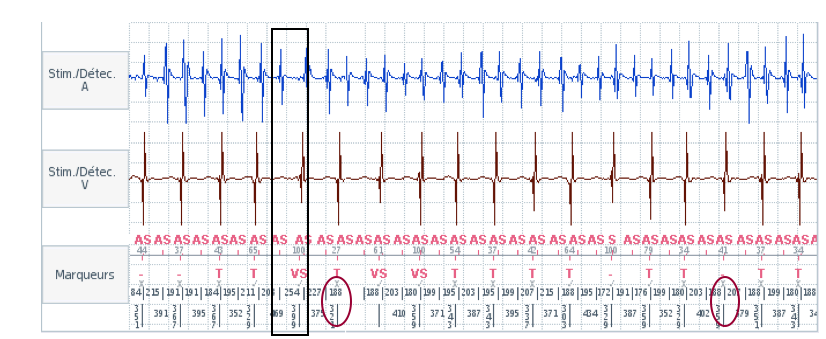

Le canal de discrimination supplémentaire SecureSense™ est activé après la détection de 2 cycles sur 3 dans la zone VT ou VF. Un compteur est incrémenté à chaque cycle court détecté sur ce canal. Si la voie de discrimination détecte des cycles courts (qui sont directement étiquetés VS² sur le tracé), le compteur est mis à zéro après chaque paire de cycles. Au moment du diagnostic, si ce compteur est ≥10, le traitement est inhibé. Le compteur est réévalué à chaque re-détection et avant l'administration d'un choc. Il est désactivé après la première thérapie.

Dans cet exemple : la stabilité ignore les intervalles les plus longs (395 ms) et les plus courts (268 ms) et soustrait le deuxième intervalle le plus long (378 ms) du deuxième intervalle le plus court (271 ms) : 378 ms - 271 ms = 107 m (> 80 ms la valeur programmée) ; la stabilité de l'intervalle indique donc une TSV (FA).